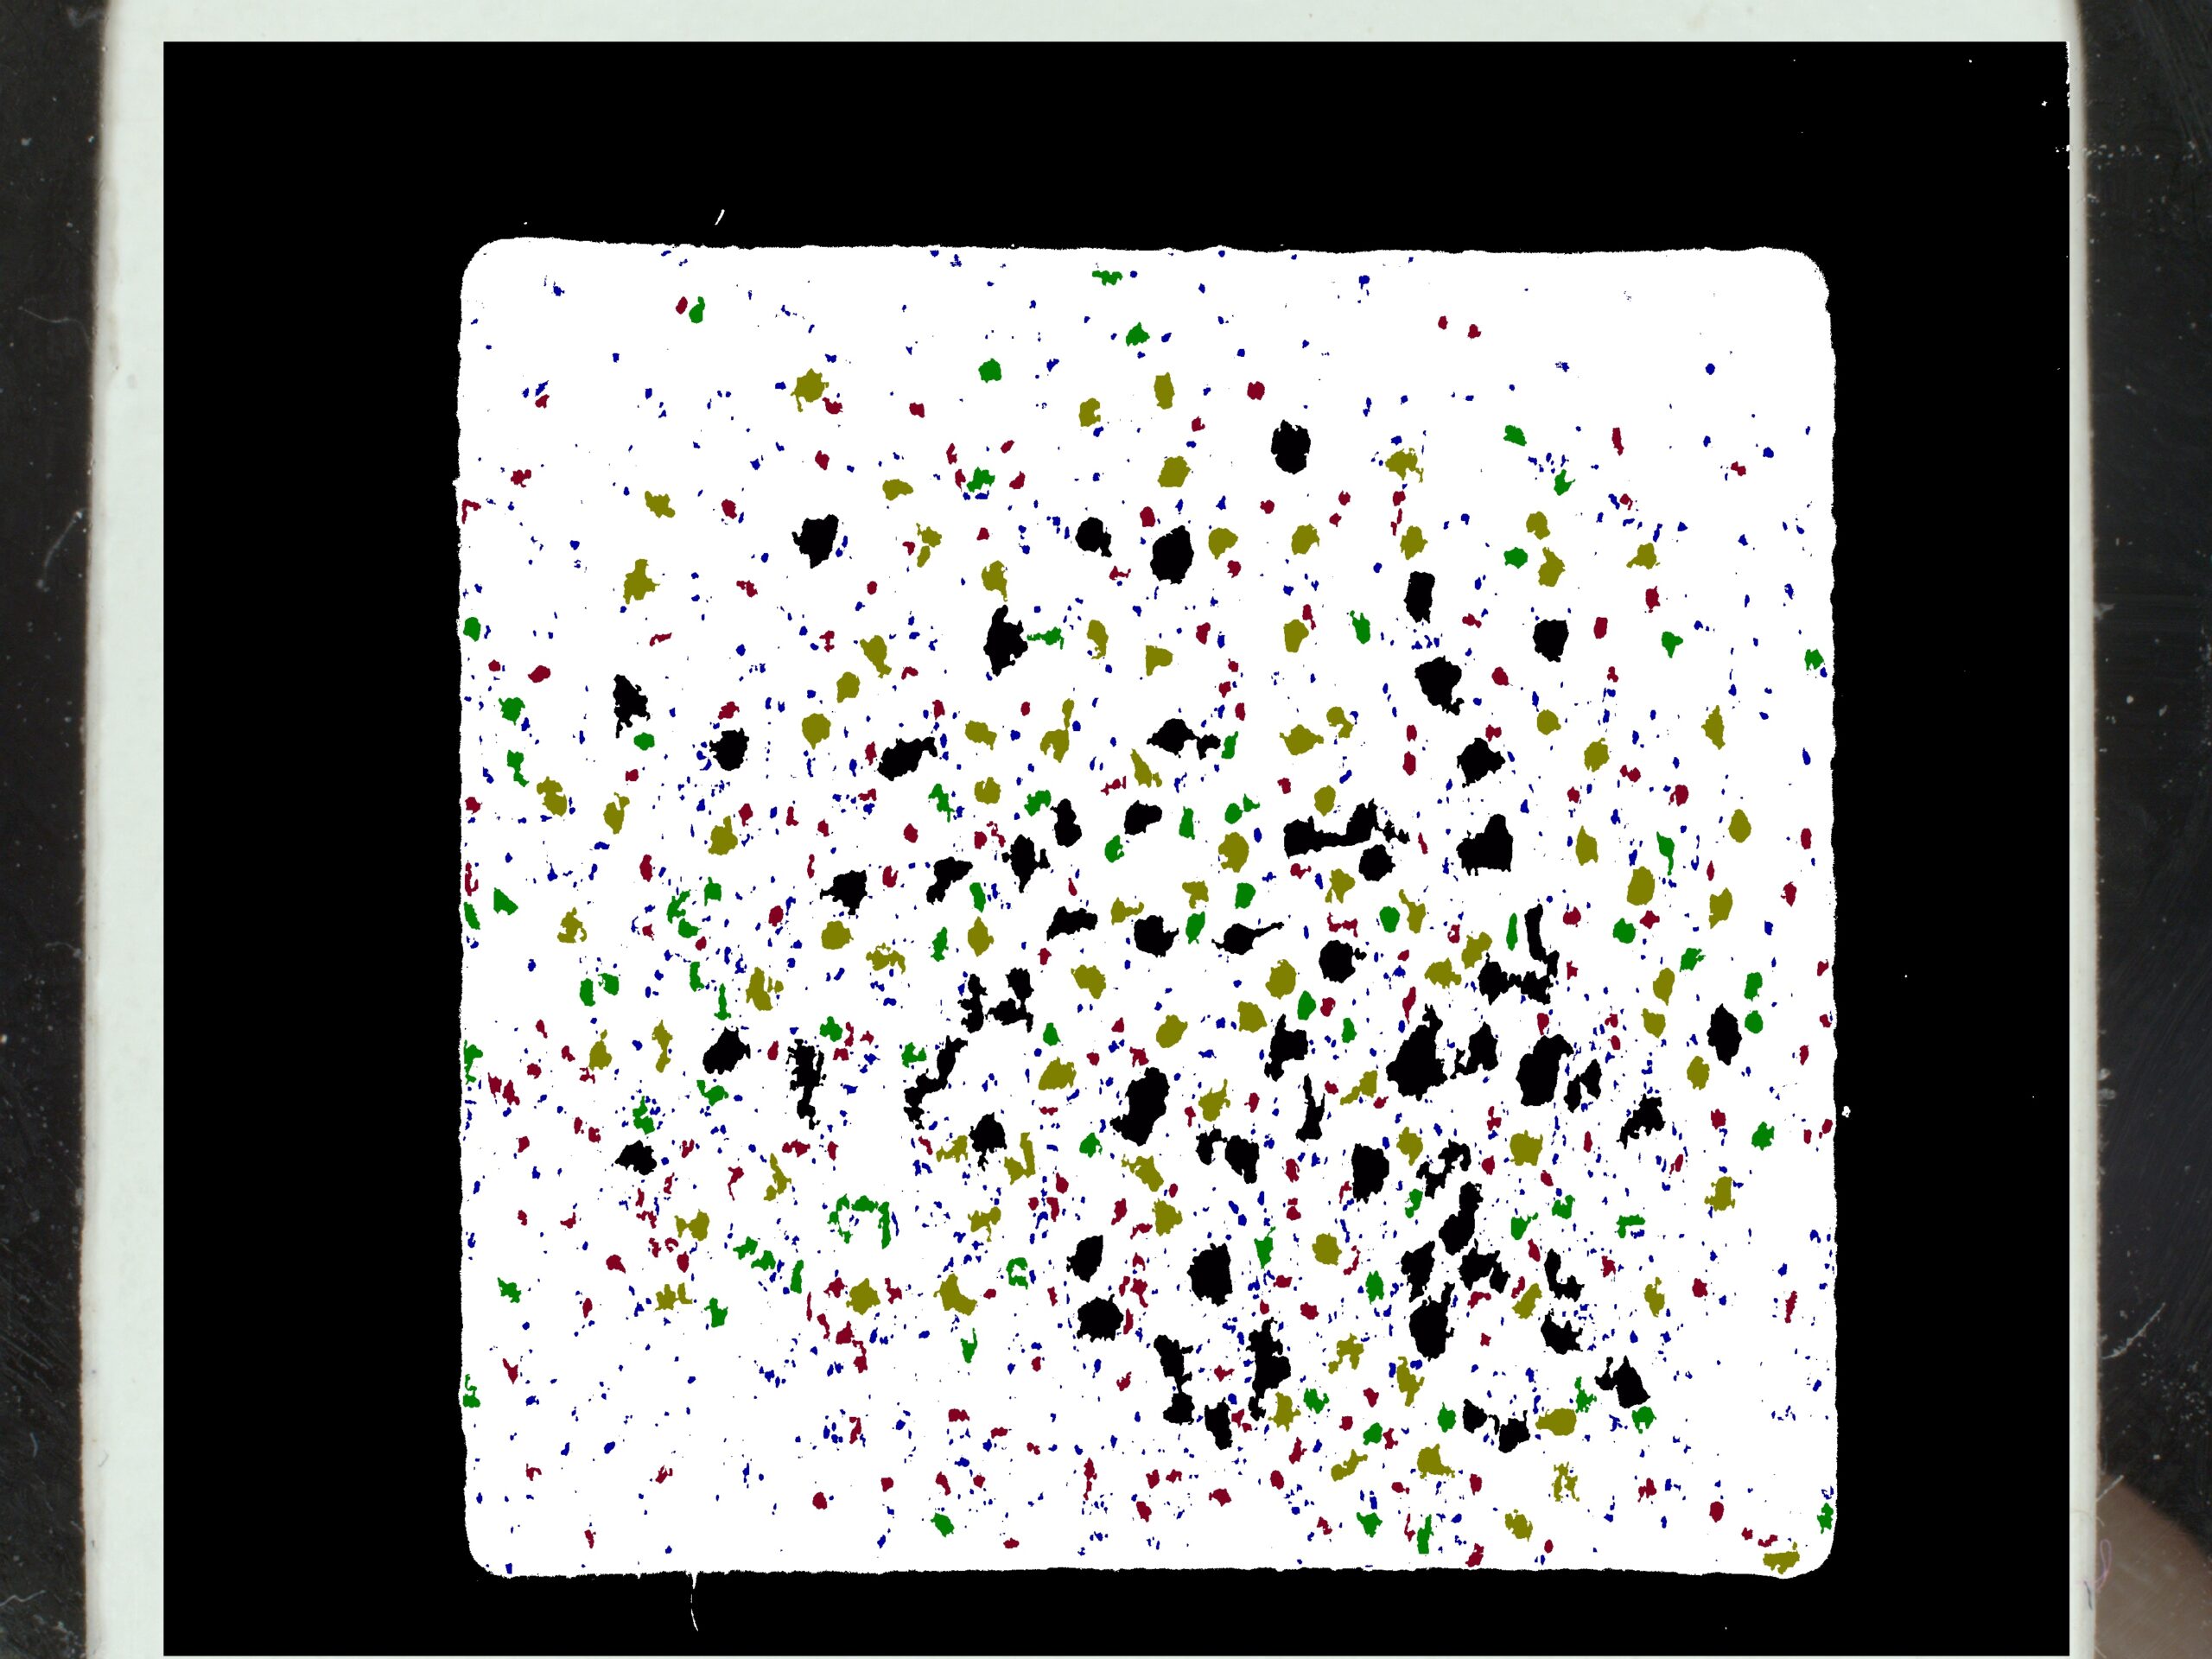

The C-Cube measures the number of black dots and the average diameter. Its field of view is constant and calibrated, meaning that the photo surface is always the same (1.92cm²). The density is therefore obtained by dividing the number of pores by the surface area of 1.92 cm².

Pores analysis

In 2D, this involves color analysis, followed by shape identification to eliminate other objects and retain only the pores. The results are images processed in black and white. You also get a spreadsheet with the median area, median diameter and pore density of each image.

Source image Processed image